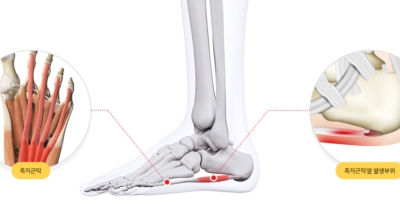

족저 근막염이란?

족저 근막이란 발가락 시작지점부터 발뒤꿈치뼈까지 발바닥 전체를 감싸고 있는 두꺼운 막을 말합니다. 족저 근막은 발바닥 아치를 지속시켜 발바닥이 지면을 내딛음으로써 발생하는 충격을 흡수하는 중요한 역할을 수행하고 있답니다. 이 족저 근막에 일차적으로 서서히 조직 손상이 일어나고 계속적인 활동으로 말미암아 염증이 커지면서 발 뒤꿈치 부근 통증을 일으키게 되는데 염증은 무리하고 반복적인 동작, 많은 사용으로 마찰에 의해 발생합니다.

족저 근막염은 염증에 의한 손상 및 통증을 유발하는 질환인데요 족저 근막염 증상은 일반적인 발뒤꿈치 통증 하글런드 병변의 기형으로 알려져 있으고 아킬레스 건과 관련이 깊다고 합니다. 특히 근육이 덜 풀린 아침 시간 대는 보행 시 날카롭고 바늘로 찌르는 듯한 심한 통증을 느끼게 된다고 합니다. 하지만 아침 시간 대를 지나 오후에 접어들면서 어느 정도 통증은 서서히 감소하기 시작한다고 하는데요 초기 증상이 나타난다면 꼭 전문의를 찾아 조기치료하는 것이 바람직합니다.